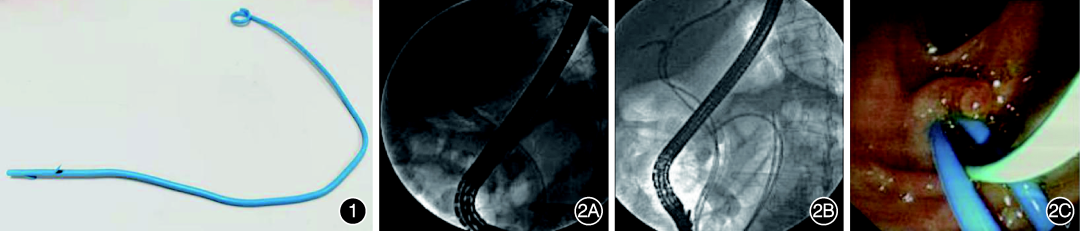

3.猪尾型鼻胆引流管改制及支架置入:首先在造影下确定狭窄位置,通过导丝测量肝内胆管梗阻端外2cm至十二指肠远端达空肠曲的长度,取1条猪尾型鼻胆管引流管(上海英诺伟公司),从猪尾鼻胆引流管圈型下方开始测量,按测量长度+1cm处截断,并于距离远端0.5cm处做侧方楔形切开形成侧翼以便引流(图1)。前端猪尾部置入肝内二级胆管分支,尾端放置到十二指肠空肠曲(图2)。针对新型支架,可以通过径向力的作用将支架的尾端送入十二指肠水平段,若放置位置不准确或存在反折,可利用异物钳调整。

1 猪尾型鼻胆引流管改制的新型胆管支架      图2 肝门部胆管癌患者经内镜逆行胰胆管造影置入新型支架置过程2A:置入支架前在胆管内注入造影剂后可见肝门部胆管狭窄;2B:置入新型胆管塑料内支架后见2枚支架分别位于肝内左右胆管,位置准确;2C:内镜下可见2枚新型胆管塑料支架位于乳头处,远端位延伸于十二指肠空肠曲